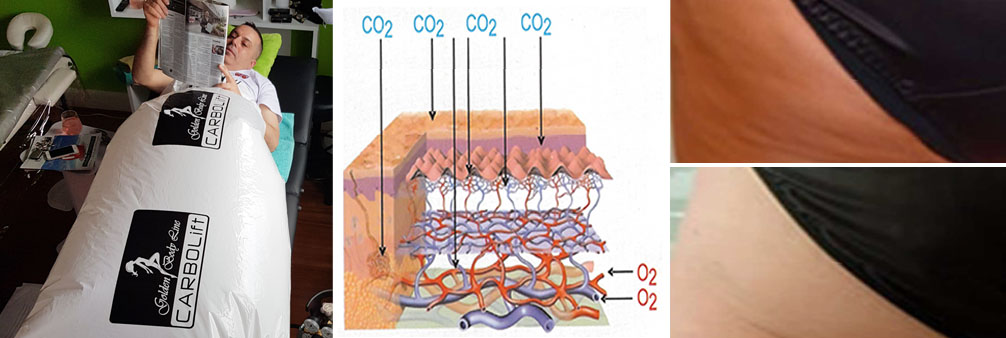

Use of HIFU technology in cosmetology has considerably increased and these days is extensively applied in lifting and rejuvenation treatments.

The apparatus therapeutic effect is based on thermal effects enabling focused ultrasound waves to precisely target tissue and the depth NOT impairing any structures through which they travel. Transformation of HIFU waves energies into thermal energies achieves therapeutic effects which are exclusively NON-ABLATIVE and BIOSTIMULATIVE enabling the treatment to stimulateneosynthesis of collagen and its regeneration and reorganisation. It also encourages neovascularization of the treated area.